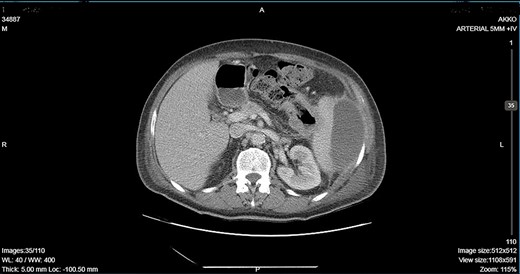

CT showing descending colon wall thickening in contact with the spleen and the tail of the pancreas and a subcapsular splenic abscess as well as splenic vein thrombosis.

A 64-year-old man presented to the emergency department with left pleuritic chest pain, anorexia and fever with rigors. His vital signs included a pulse of 130 beats/min, blood pressure of 108/51 mmHg, respiratory rate of 18 breaths/min, oxygen saturation of 95% and body temperature of 36.1°C. He had no relevant medical history. The patient was admitted to the hospital with the diagnosis of pneumonia based on his chest X-ray findings. The patient remained hemodynamically stable through the next day but developed a temperature of 39.2°C. A CT scan revealed a tumor of the splenic flexure that had invaded the spleen and pancreas via the transcoelomic route and created a subcapsular splenic abscess (Fig. 1). The CT scan also revealed splenic vein thrombosis located proximal to the tail of the pancreas. CT-guided percutaneous drainage of the abscess was scheduled for the following day. The patient’s clinical condition suddenly deteriorated and he became hemodynamically unstable. Abdominal distention with diffuse tenderness was identified via clinical examination, and laboratory tests revealed leukocytosis with a white blood cell count of 16.800/mm and anemia, with a hematocrit of 28.5%. An emergent CT scan revealed intraperitoneal rupture of the splenic abscess (Fig. 2). Intraoperative findings of an urgent surgical intervention included severe, diffuse purulent peritonitis with a large amount of pus mixed with blood clots in the peritoneal cavity that required cautious cleaning and thorough lavage. Furthermore, a large, hard, immovable tumor was identified in the splenic flexure of the colon. The tumor was tightly adherent to the spleen; we also noted the presence of intense inflammation and local fibrosis that extended to the surrounding tissues. En-block splenectomy and a wide left colectomy were performed followed by closure of the distant colon remnant using a linear stapler; furthermore, we also created an ostomy of the proximal colon remnant, similar to Hartmann’s procedure and drained the abdominal cavity. Transfusion of 600 ml of red blood cells was required. Extubation and postoperative recovery were uneventful, and the patient’s clinical status and parameters remained stable. Antibiotic treatment included meropenem 2 g thrice daily, metronidazole 500 mg thrice daily and amikasin 1 g once daily. The postoperative course was uneventful and the patient was discharged on postoperative day 12. Histopathological examination of the resected specimen revealed a 6 cm diameter perforated tumor adherent to an 18 × 13 × 6 cm spleen and a moderately differentiated grade 2 adenocarcinoma with infiltration to the pericolic fat. The resection margins were free of infiltration as were all of the 19 resected lymph nodes. A metastatic tumor, 2 cm in diameter, was identified in the spleen portal. The TNM stage was T3N0M1a (stage IVA disease), and the patient was referred to the Oncologic Department for adjuvant chemotherapy. He was administered eight cycles of Capecitabine that is changed into 5-fluorouracile + Oxaliplatin along with the necessary follow-up care. The patient has been disease-free for 2 years after the treatment.